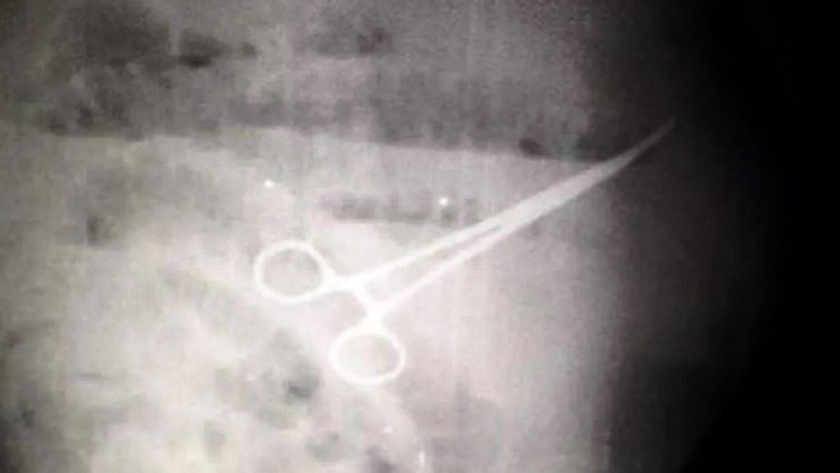

В середине апреля 2022 года в Венесуэле пациент умер после того, как нерадивые хирурги оставили ножницы в его желудке во время операции. Родственники умершего утверждает, что медики скрывали от них его истинное состояние и пытались сделать вид, что все прошло без проблем.

Иван Чавес, 59 лет, обратился в Университетскую больницу Маракайбо, второго по величине города Венесуэлы, для операции на желудке. Операция по удалению воспаленного дивертикула была признана успешной, но вскоре после операции пациент начал испытывать боли в животе, ему стало трудно употреблять пищу и ходить в туалет.

Врачи назначили Ивану Чавесу различные методы лечения. Однако дискомфорт не проходил, и через четыре дня после операции медицинский персонал решил сделать рентген, тогда-то медицинский персонал и обнаружили, что хирурги оставили в желудке пациента ножницы. Чавесу была проведена экстренная операция по извлечению ножниц, которая, опять же, была признана полностью успешной. Но через пять дней Чавес умер, и его семья, как сообщается, обвинила в этом нерадивых хирургов.